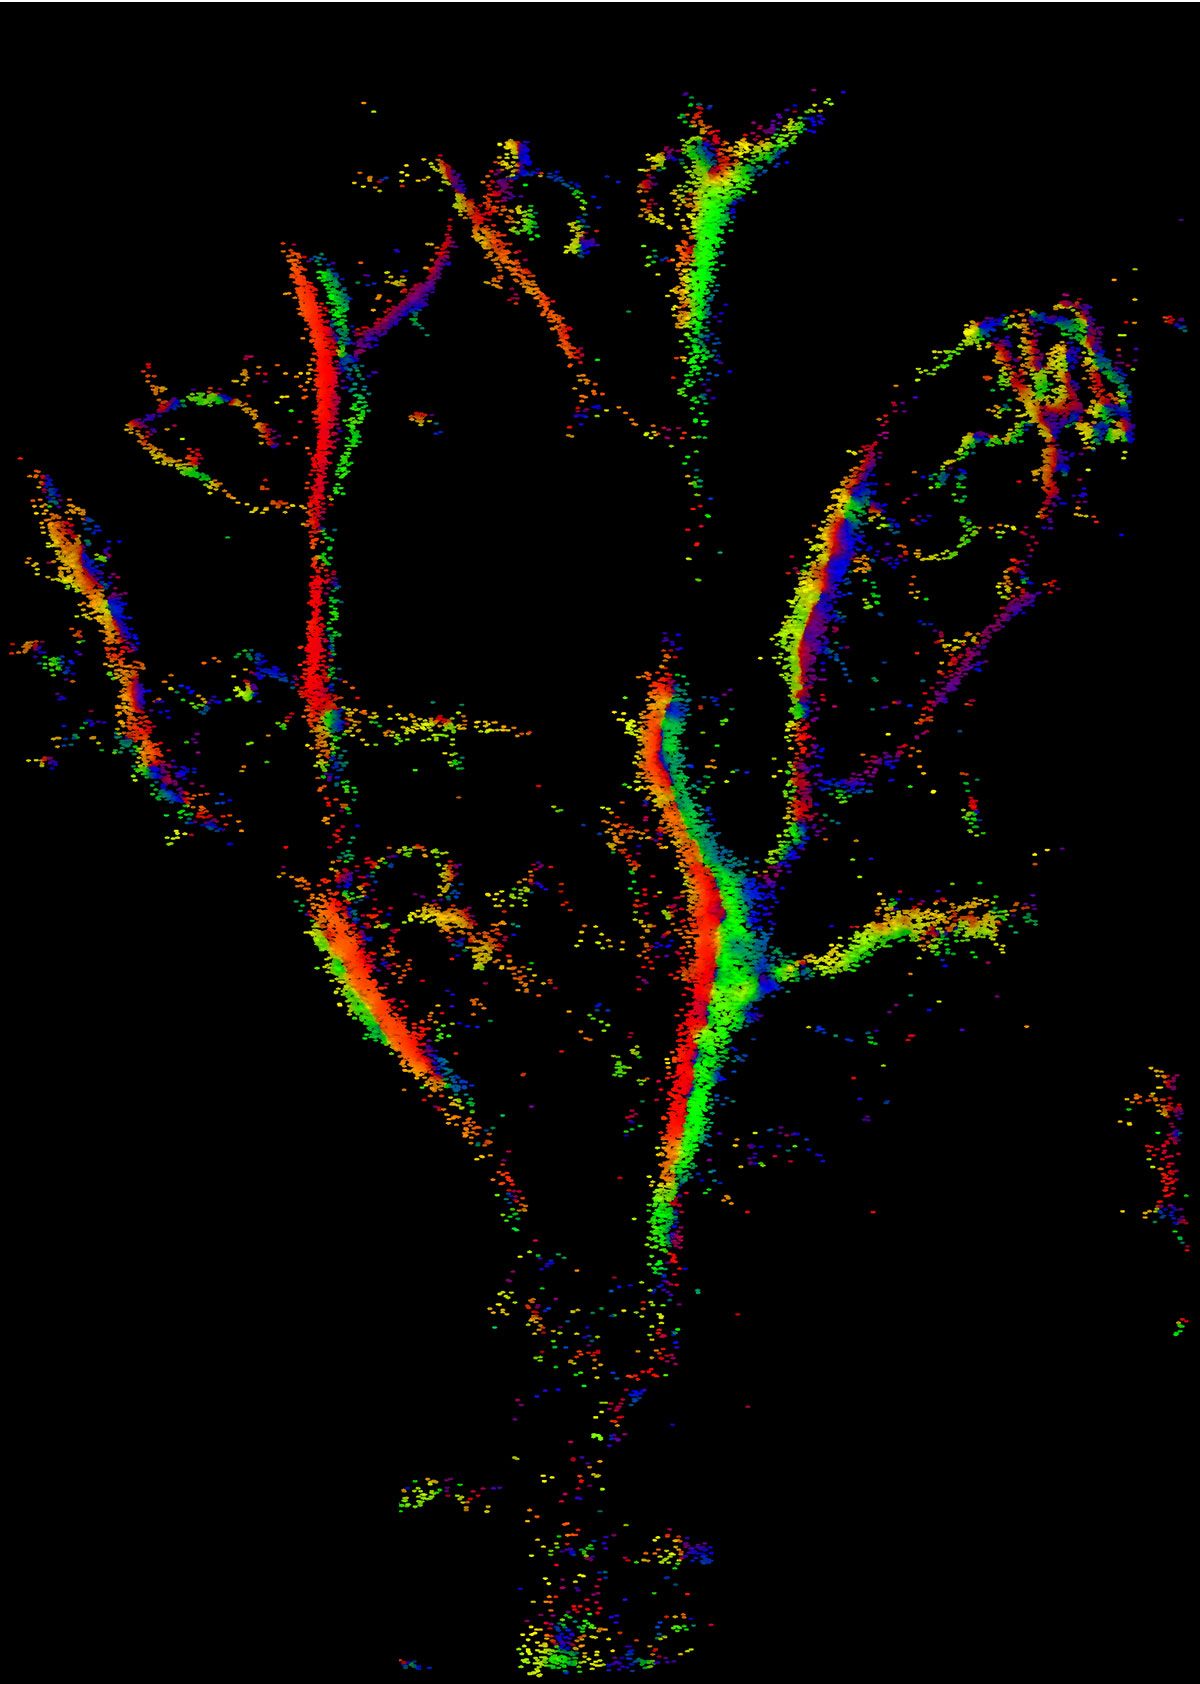

To create this image, Kirsten Christensen-Jeffries and colleagues from King's College London used standard ultrasound imaging to peer into the minute blood vessels in a mouse's ear. They added bubbles as small as red blood cells – less than 10 micrometres across – to locate the veins more accurately than ever before.

The image also reveals blood flow. The colours represent the direction blood is travelling in adjacent veins, and greater brightness indicates faster speed.

The ability to see such small blood vessels could some day help doctors detect early signs of damage in the circulatory system or map new veins that signal the growth of a cancerous tumour. The next step will be creating the images in real time – this one took about 10 minutes to produce, including computer processing.